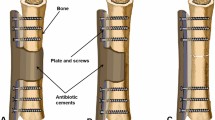

Plates or intramedullary nails were used to fix the defect end according to different bone defect sites and intramedullary infection. The broken end of the defect was filled with polymethyl methacrylate (PMMA) bone cement containing gentamicin. Subsequently, 2 g of antibiotic (vancomycin or imipenem) powder was added to 40 g cement powder, fully crushed, stirred evenly, and then mixed well with the liquid monomer. When the mixed antibiotic bone cement was in the dough stage, the bone defect was filled, the internal fixation plate or intramedullary nail was wrapped and extended 5–6 cm to the proximal and distal ends of the bone defect, and the bone cement was smoothed. When the bone cement solidified and heated up, ice-cold saline was used for flushing to reduce thermal damage to surrounding tissues. A typical case is shown in Fig. 1.

A infected limb with sinus and external fixator before the surgery. B X-ray of infected femoral bone before the surgery. C After a thorough debridement, antibiotic bone cement–coated nail and plate were used to stabilize the bone fracture, and the bone defect was filled with antibiotic cement spacer. From left to right: bone cement–coated K-wire was placed in the femoral medullary cavity. The steel plate was attached to the outside for reinforcement. D X-ray of the mid and lower level of the femoral cavity during the surgery. E, F Pictures after stage I surgery. G, H Autologous iliac bone graft combined with calcium sulfate and calcium phosphate composite materials filled into the bone defect cavity. I, J Post-operative X-ray and the incision healed at the 3-month follow-up